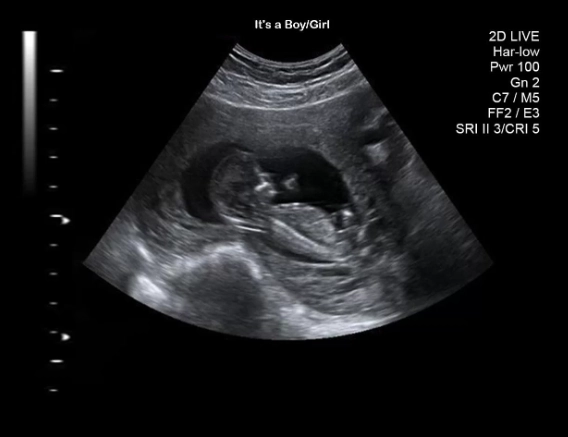

You might have had an earlier scan around 6-8 weeks, maybe to confirm the pregnancy or check the heartbeat. That one's important, sure, but it's often just a little blob and a flicker. The 12 weeks pregnant ultrasound is different. It's the first major, detailed check-up for your baby. Think of it as the end of the first trimester graduation exam.

They'll point things out as they go: "There's the head," "See the heartbeat flickering," "Those are the little arm buds moving." You'll likely see your baby bouncing, stretching, or even sucking its thumb. It's utterly mesmerizing.

This is the headline act. The sonographer will zoom in for a perfect side-profile view of the baby and measure the translucent (fluid-filled) space at the back of the neck in millimeters. The measurement increases naturally with the baby's size, so it's assessed against the crown-rump length.